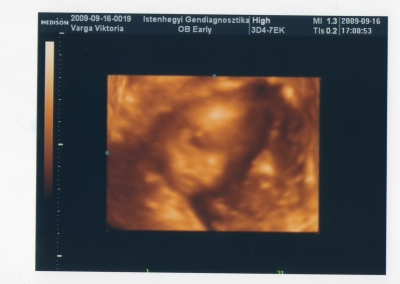

Drága kislányunk pofija a 18 hetes genetikai uh-n.

Kép